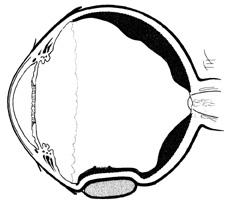

Medical attempts to lower pressure usually are effective only for relatively small buckles. For circumferential buckles extending more than one quadrant, intraocular volume must be removed surgically. In phakic eyes, anterior chamber paracentesis can remove up to 0.3 to 0.4 mL of aqueous at one time. Paracentesis is performed under magnification at the limbus with a blade, which is passed in a shelved manner through the cornea, entering the anterior chamber over the iris to protect the lens. The blade then is rotated, thereby opening the wound to allow aqueous to egress. The depth of the anterior chamber is closely monitored to prevent damage to the lens. When enough drainage has been obtained, the blade is turned back to its original entering position. This closes the corneal wound and minimizes the chance of iris incarceration as the blade is removed. The corneal wound is self-sealing (Fig. 34). This technique is effective also in pseudophakic patients with posterior chamber intraocular lenses and intact posterior capsules or capsulotomies sealed by the intraocular lens. Alternatively, a 30-gauge needle can be used to remove aqueous.

Fig. 34. Anterior chamber paracentesis technique using limbal approach.